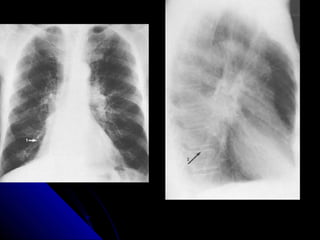

FFiibbrroossiiss

LLooookk aatt tthhee ssiizzee ooff tthhee lluunngg..

LLooookk aatt tthhee ddiissttrriibbuuttiioonn..

LLooookk aatt tthhee ppoossiittiioonn ooff tthhee mmeeddiiaassttiinnuumm..

LLooookk aatt tthhee bboorrddeerrss ooff tthhee hheeaarrtt aanndd tthhee

ddiiaapphhrraaggmm..